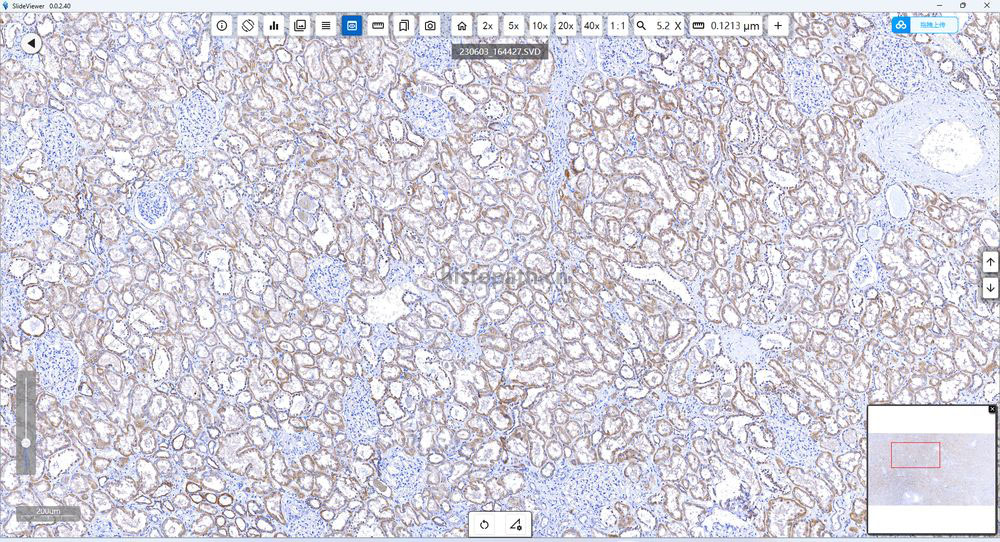

结果:阳性部位棕褐色,细胞核天蓝色,对比鲜明,无背景着色。

SP1.jpg    免疫组化(肾).jpg